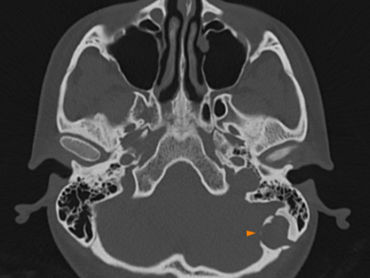

A Mystery in the Mastoid Bone: Intradiploic Epidermoid Cyst Case No: NR.1.5.1.2.002

Clinical Profile Patient: 25-year-old female. Presentation: Slow-growing, painless, firm swelling in the left mastoid region. Radiological Findings: 1. CT: The Architecture A well-defined, lytic lesion significantly expanding the outer table of the left mastoid bone. The sclerotic margins indicate a slow-growing, benign process. 2. MRI: Tissue Identity T1W Axial T2W Axial T1: Hypointense. T2: Heterog eneously hyperintense. Contrast T1: No internal enhancement, but minimal p